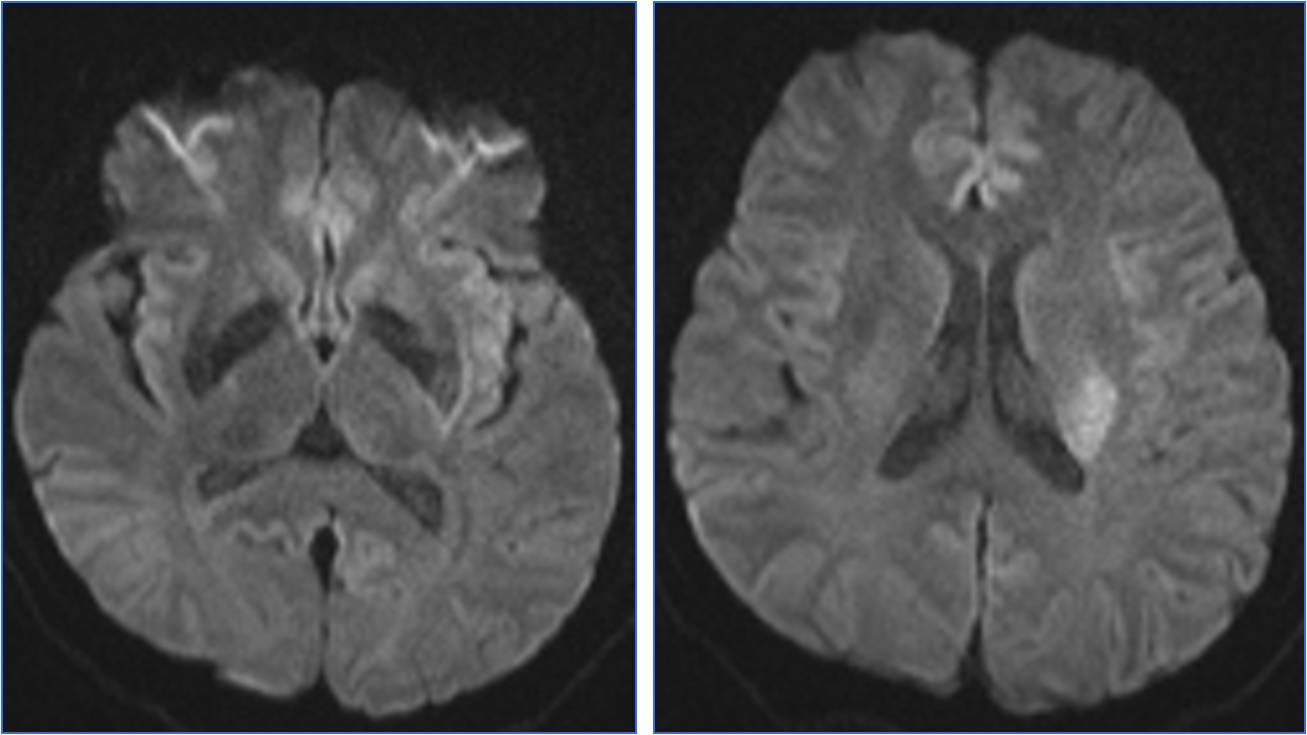

▼11:11复查头CT

▼11:56头MRA

》准备介入血管内治疗,患者症状自行缓解。后又加重,症状波动2次。

》13:22进入导管室行血管内治疗。行气管插管全身麻醉。

》DSA见基底动脉闭塞,Solitaire支架取栓后见基底动脉重度狭窄,Gateway球囊扩张,置入Wingspan支架。

》术后24h完全恢复,NIHSS评分0分。

▼13:49DSA

▼支架取栓后基底动脉残余重度狭窄

▼基底动脉支架置入术

▼4天后复查MRA